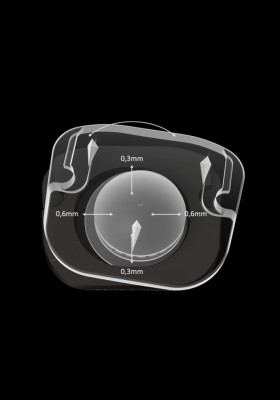

El portaimplante radiotransparente permite verificar la posición anterior de la prótesis y confirmar la precisión del ajuste. Gracias a este instrumento, la prótesis se entrega premontada para facilitar la manipulación.

El núcleo de polietileno con movilidad controlada está diseñado para reducir la carga excesiva

en las articulaciones facetarias. Permite 6 grados de libertad.

Distribución de la presión por contacto significativamente inferior en el núcleo central de polietileno.